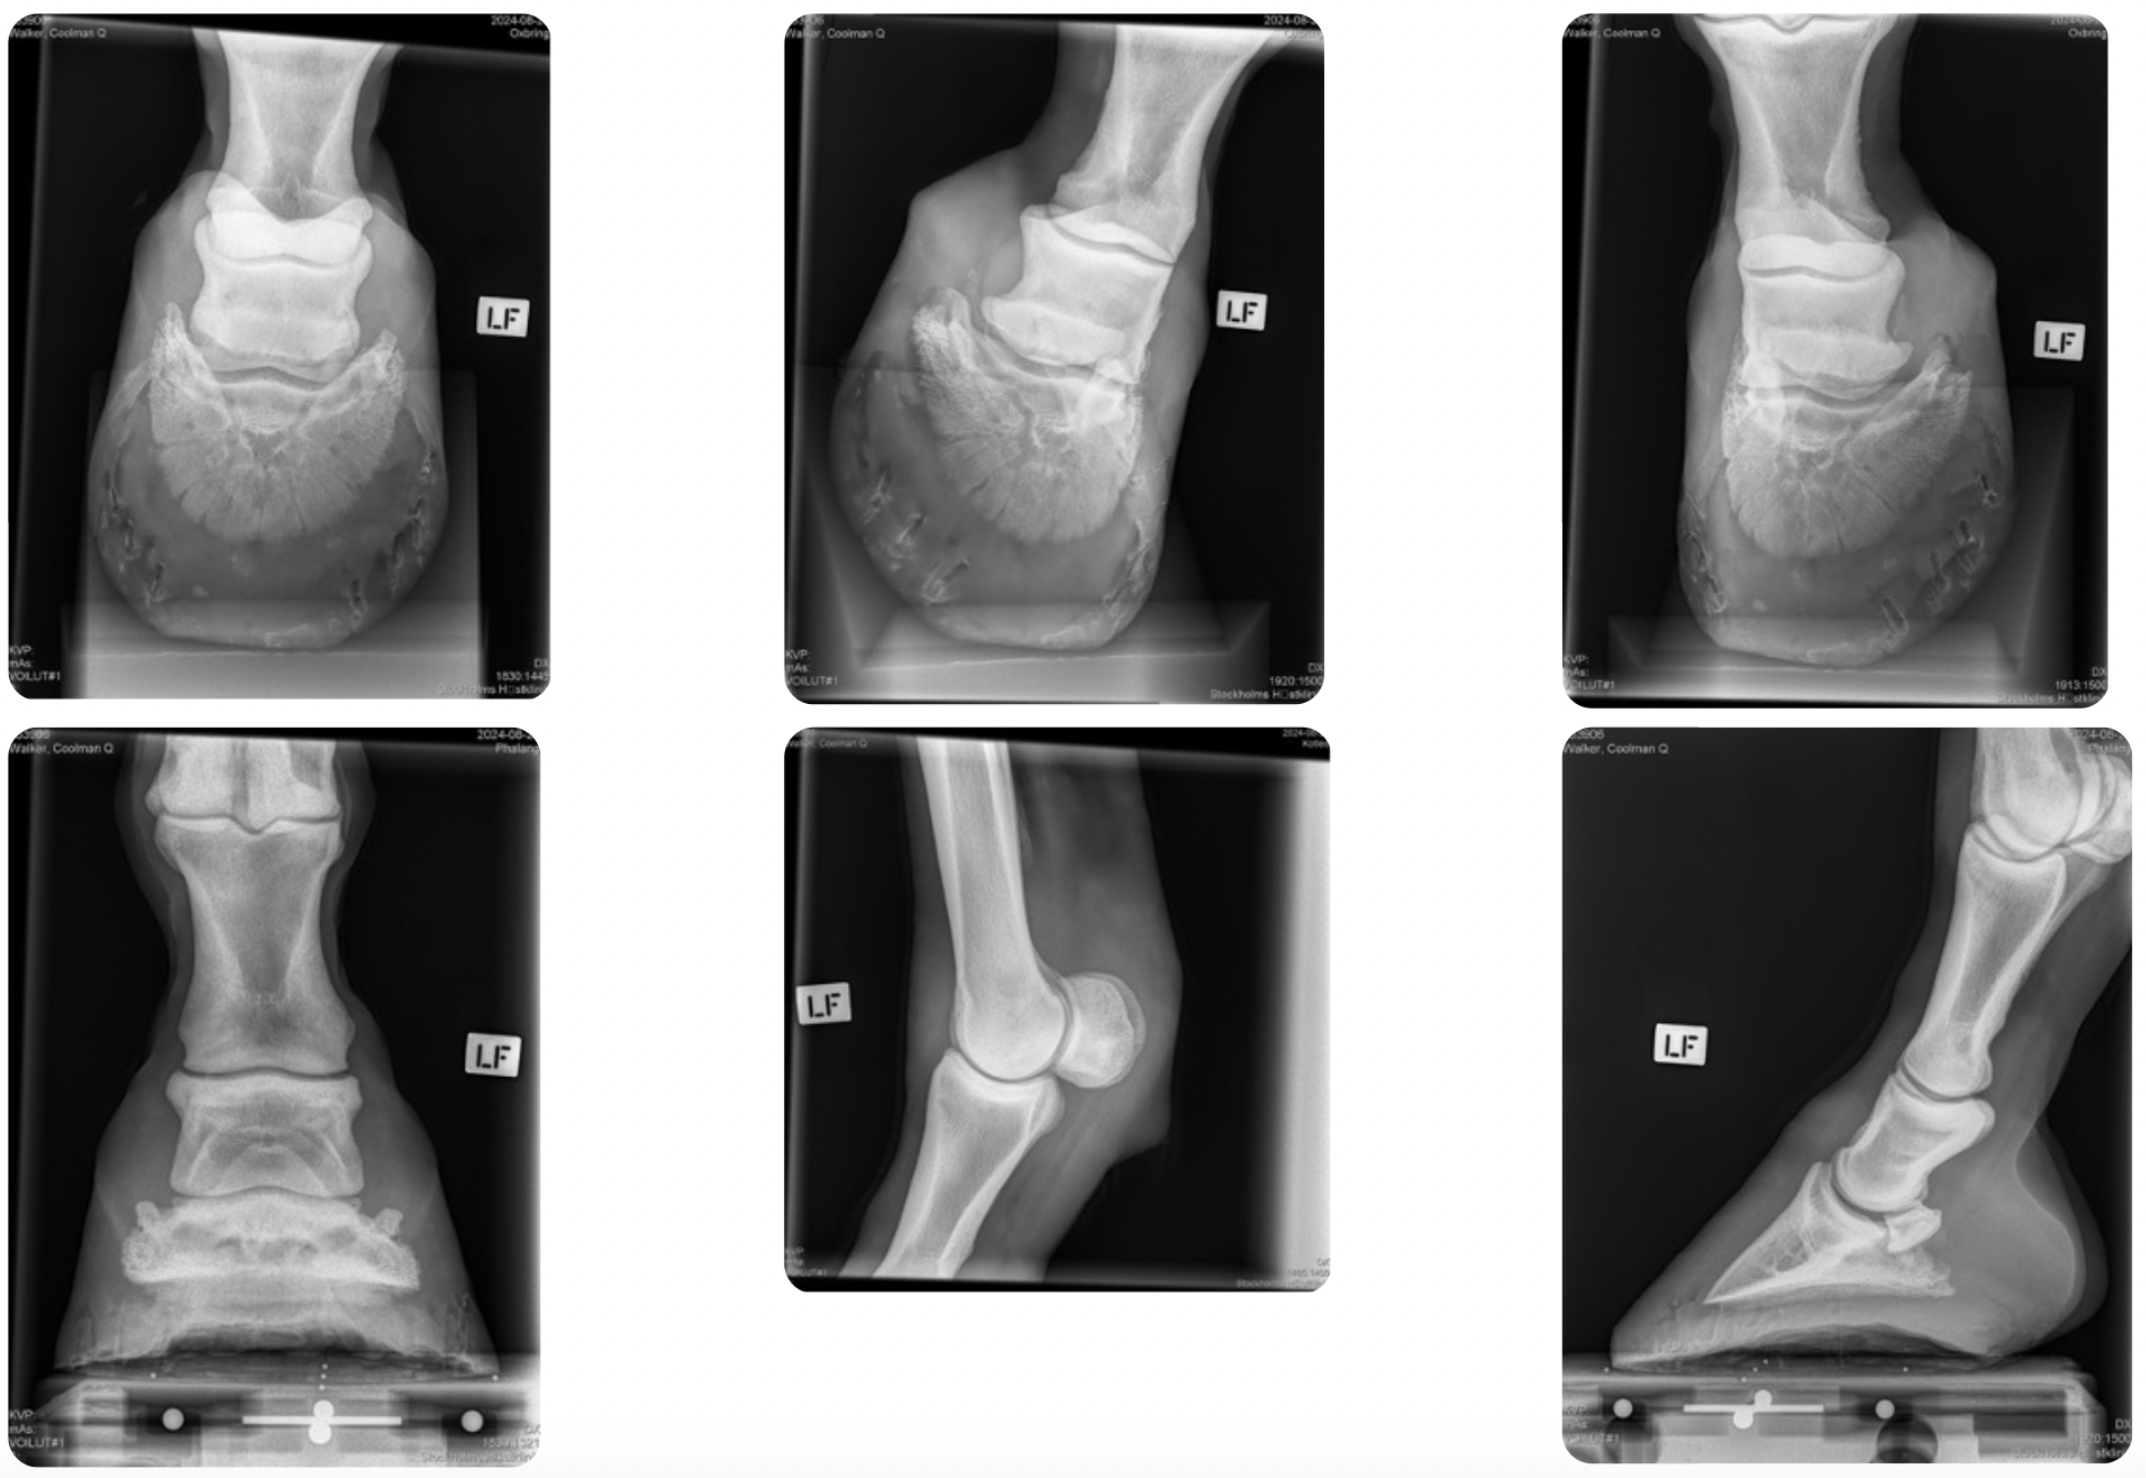

Upon examination with X-ray and ultrasound, Coolman Q was found to have a bulging medial lobe of the distal deep digital flexor tendon (DDFT) with a hypoechoic lesion on the palmar aspect at the level of P1. A positive Doppler signal was detected in the corresponding area as well as in the distal aspect of the DDFT, where the signal was more dorsally evident.

X-rays revealed mild synovial invaginations of the navicular bone, particularly on the medial aspect, along with slight remodeling of the palmar part of the navicular bone and a mild-to-moderate osteophyte on the proximal P1.The DDFT lesion was considered the most clinically relevant finding. Coolman Q was referred for an MRI of the left forelimb to assess the extent of the lesion.